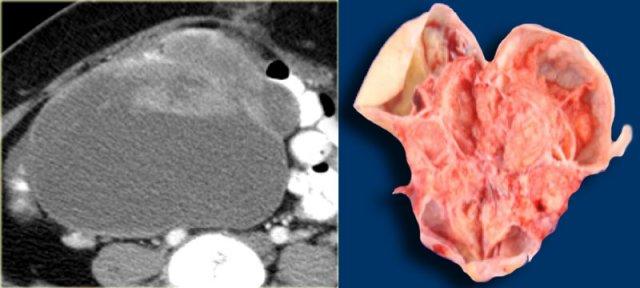

Trường hợp tiếp theo là siêu âm qua thành bụng cho thấy một khối nang đa thùy bên trái.

Hình ảnh này gợi ý u nang tân sinh buồng trứng nhưng không xác định được buồng trứng.

CT trên cùng bệnh nhân cho thấy một khối nang đa thùy tiếp giáp bàng quang, có liên quan đến tĩnh mạch buồng trứng trái (mũi tên).

Có các vách ngăn dày và thành dày không đều.

Dựa trên hình ảnh CT này, không thể phân biệt giữa tổn thương buồng trứng lành tính như u nang tuyến xơ và tổn thương buồng trứng ác tính.

Tổn thương được phẫu thuật cắt bỏ và kết quả giải phẫu bệnh xác định là u nang tuyến xơ.